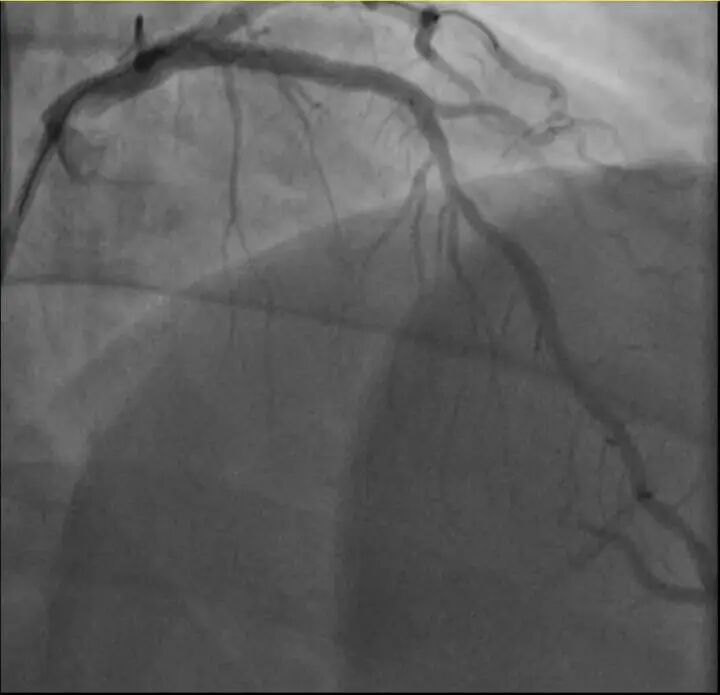

浙江医院心血管内科副主任汤益民主任医师分析,剧烈运动导致这位患者心脏的不稳定斑块破裂,进而造成前降支近段次全闭塞。所幸送医及时,接受紧急介入治疗后,孙先生的身体险情被成功化解。

介入治疗前后影像图